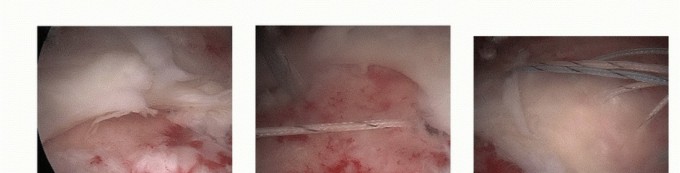

Treatment of Recurrent Posterior Shoulder Instability DEFINITION Symptomatic recurrent posterior instability …